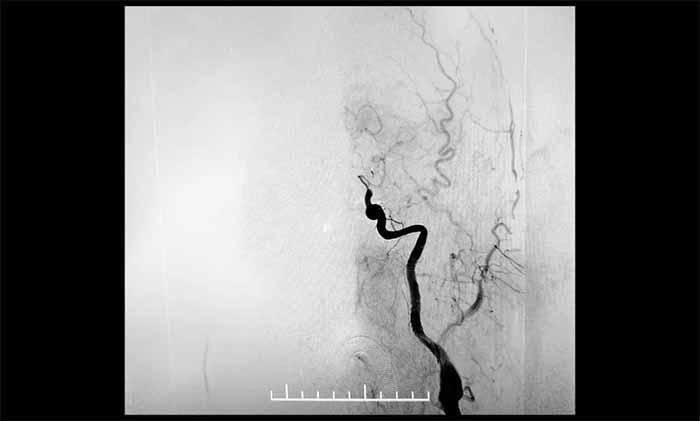

▲ DSA显示,左颈内动脉C7段闭塞